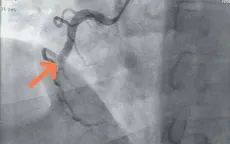

Cấp cứu bệnh nhân nhồi máu cơ tim cấp, tắc hoàn toàn động mạch chính nuôi tim

VTV.vn - Đau ngực âm ỉ liên tục, cảm giác bóp nghẹt ở tim, nam bệnh nhân 62 tuổi nguy kịch đã được hồi sinh tại Khoa Tim mạch, Bệnh viện Đa khoa Hùng Vương (Phú Thọ).